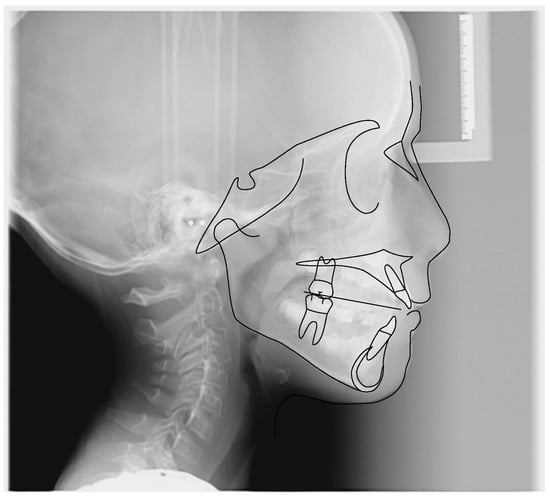

3.1. Clinical Case #1

3.2. Clinical Case #2

3.3. Clinical Case #3

3.4. Clinical Case #4